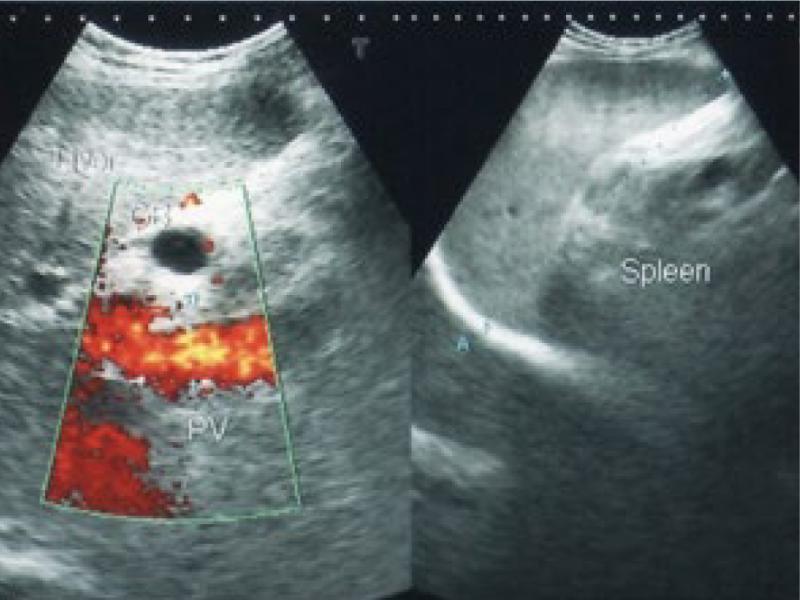

Fig. 1.